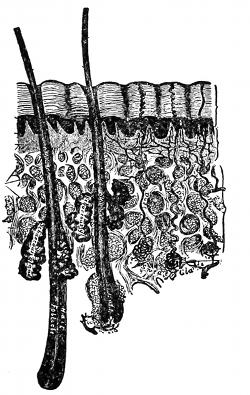

The Hair.

—The hair, like the nails, is a peculiar modification

of the epidermis and consists of practically the

same cellular structure as the epidermis. Hair is found

on nearly every part of the body excepting the palms

of the hands and the soles of the feet, the borders of

the lips, etc. It varies much in length, thickness and in

the different races of mankind. In the eyelids it is short,

on the scalp it is of considerable length. In other parts

as the eye-lashes, the hair of the pubis region, the whiskers

and beard the thickness is remarkable.

A hair consists of the root and the shaft. The root

[42]

of the hair or that part implanted in the skin presents

at its extremity a bulbous enlargement, called the hair

bulb. Into this bulb we find the small arterial capillary

circulating and at its termination the beginning of the

venous capillary. In this way the hair is nourished in

life. We also find a small nerve going to the hair bulb.

The shaft is the remaining part or that part coming out

from the skin.